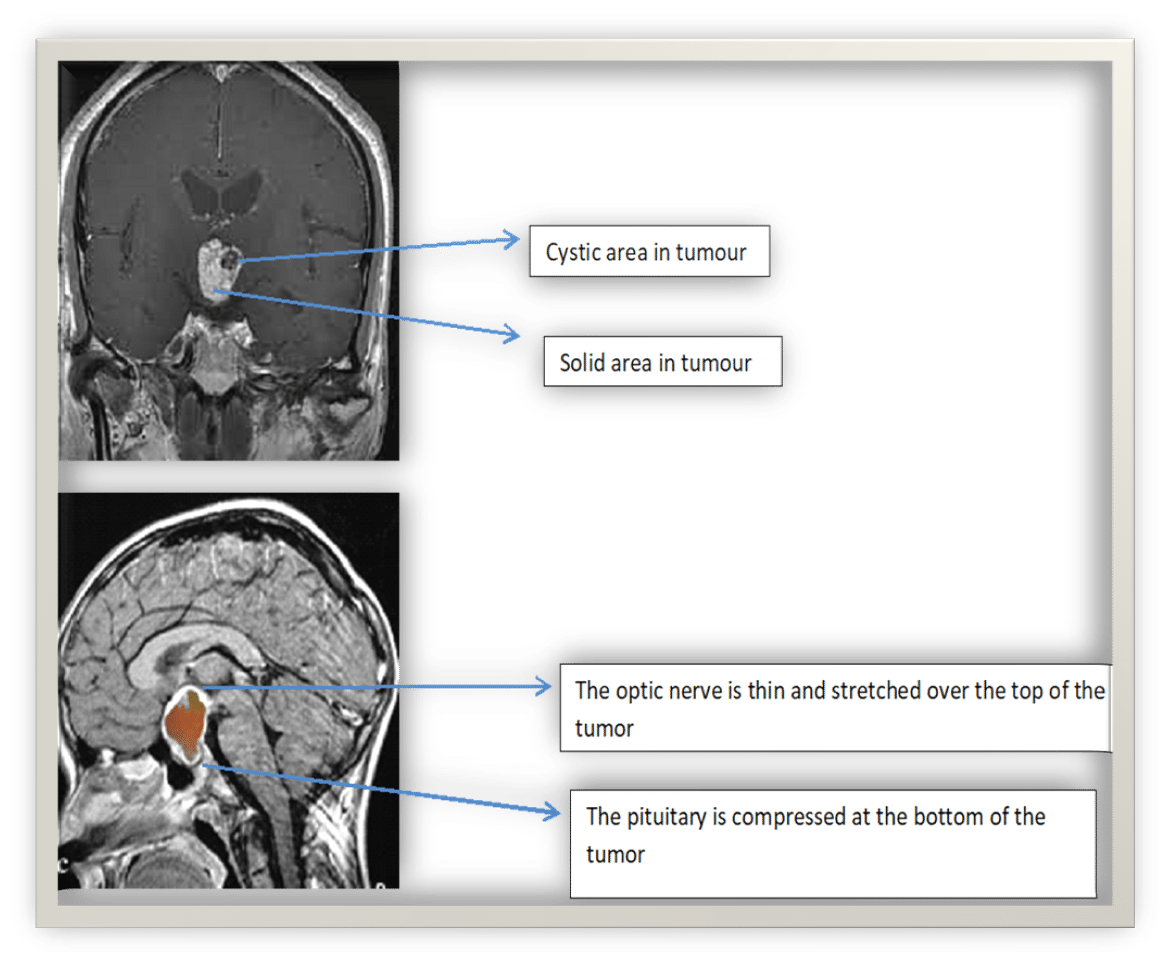

Craniopharyngiomas are usually large when discovered on magnetic resonance imaging (MRI). They are identified by having both cystic and solid parts. They are often found when they grow up and out of the pituitary and around the optic nerve or the optic chiasm where the nerves from the eyes cross and enter the brain affecting vision. They may also grow between the pituitary and the hypothalamus, impacting the hypothalamus causing symptoms such as weight gain. If they grow into the area beside the pituitary, the cavernous sinus, they may affect the movement and ability of the eyes to focus.

MRI confirms the presence of a tumor. These tumors have a characteristic appearance on Magnetic Resonance Imaging (MRI) with both cystic areas and solid areas.